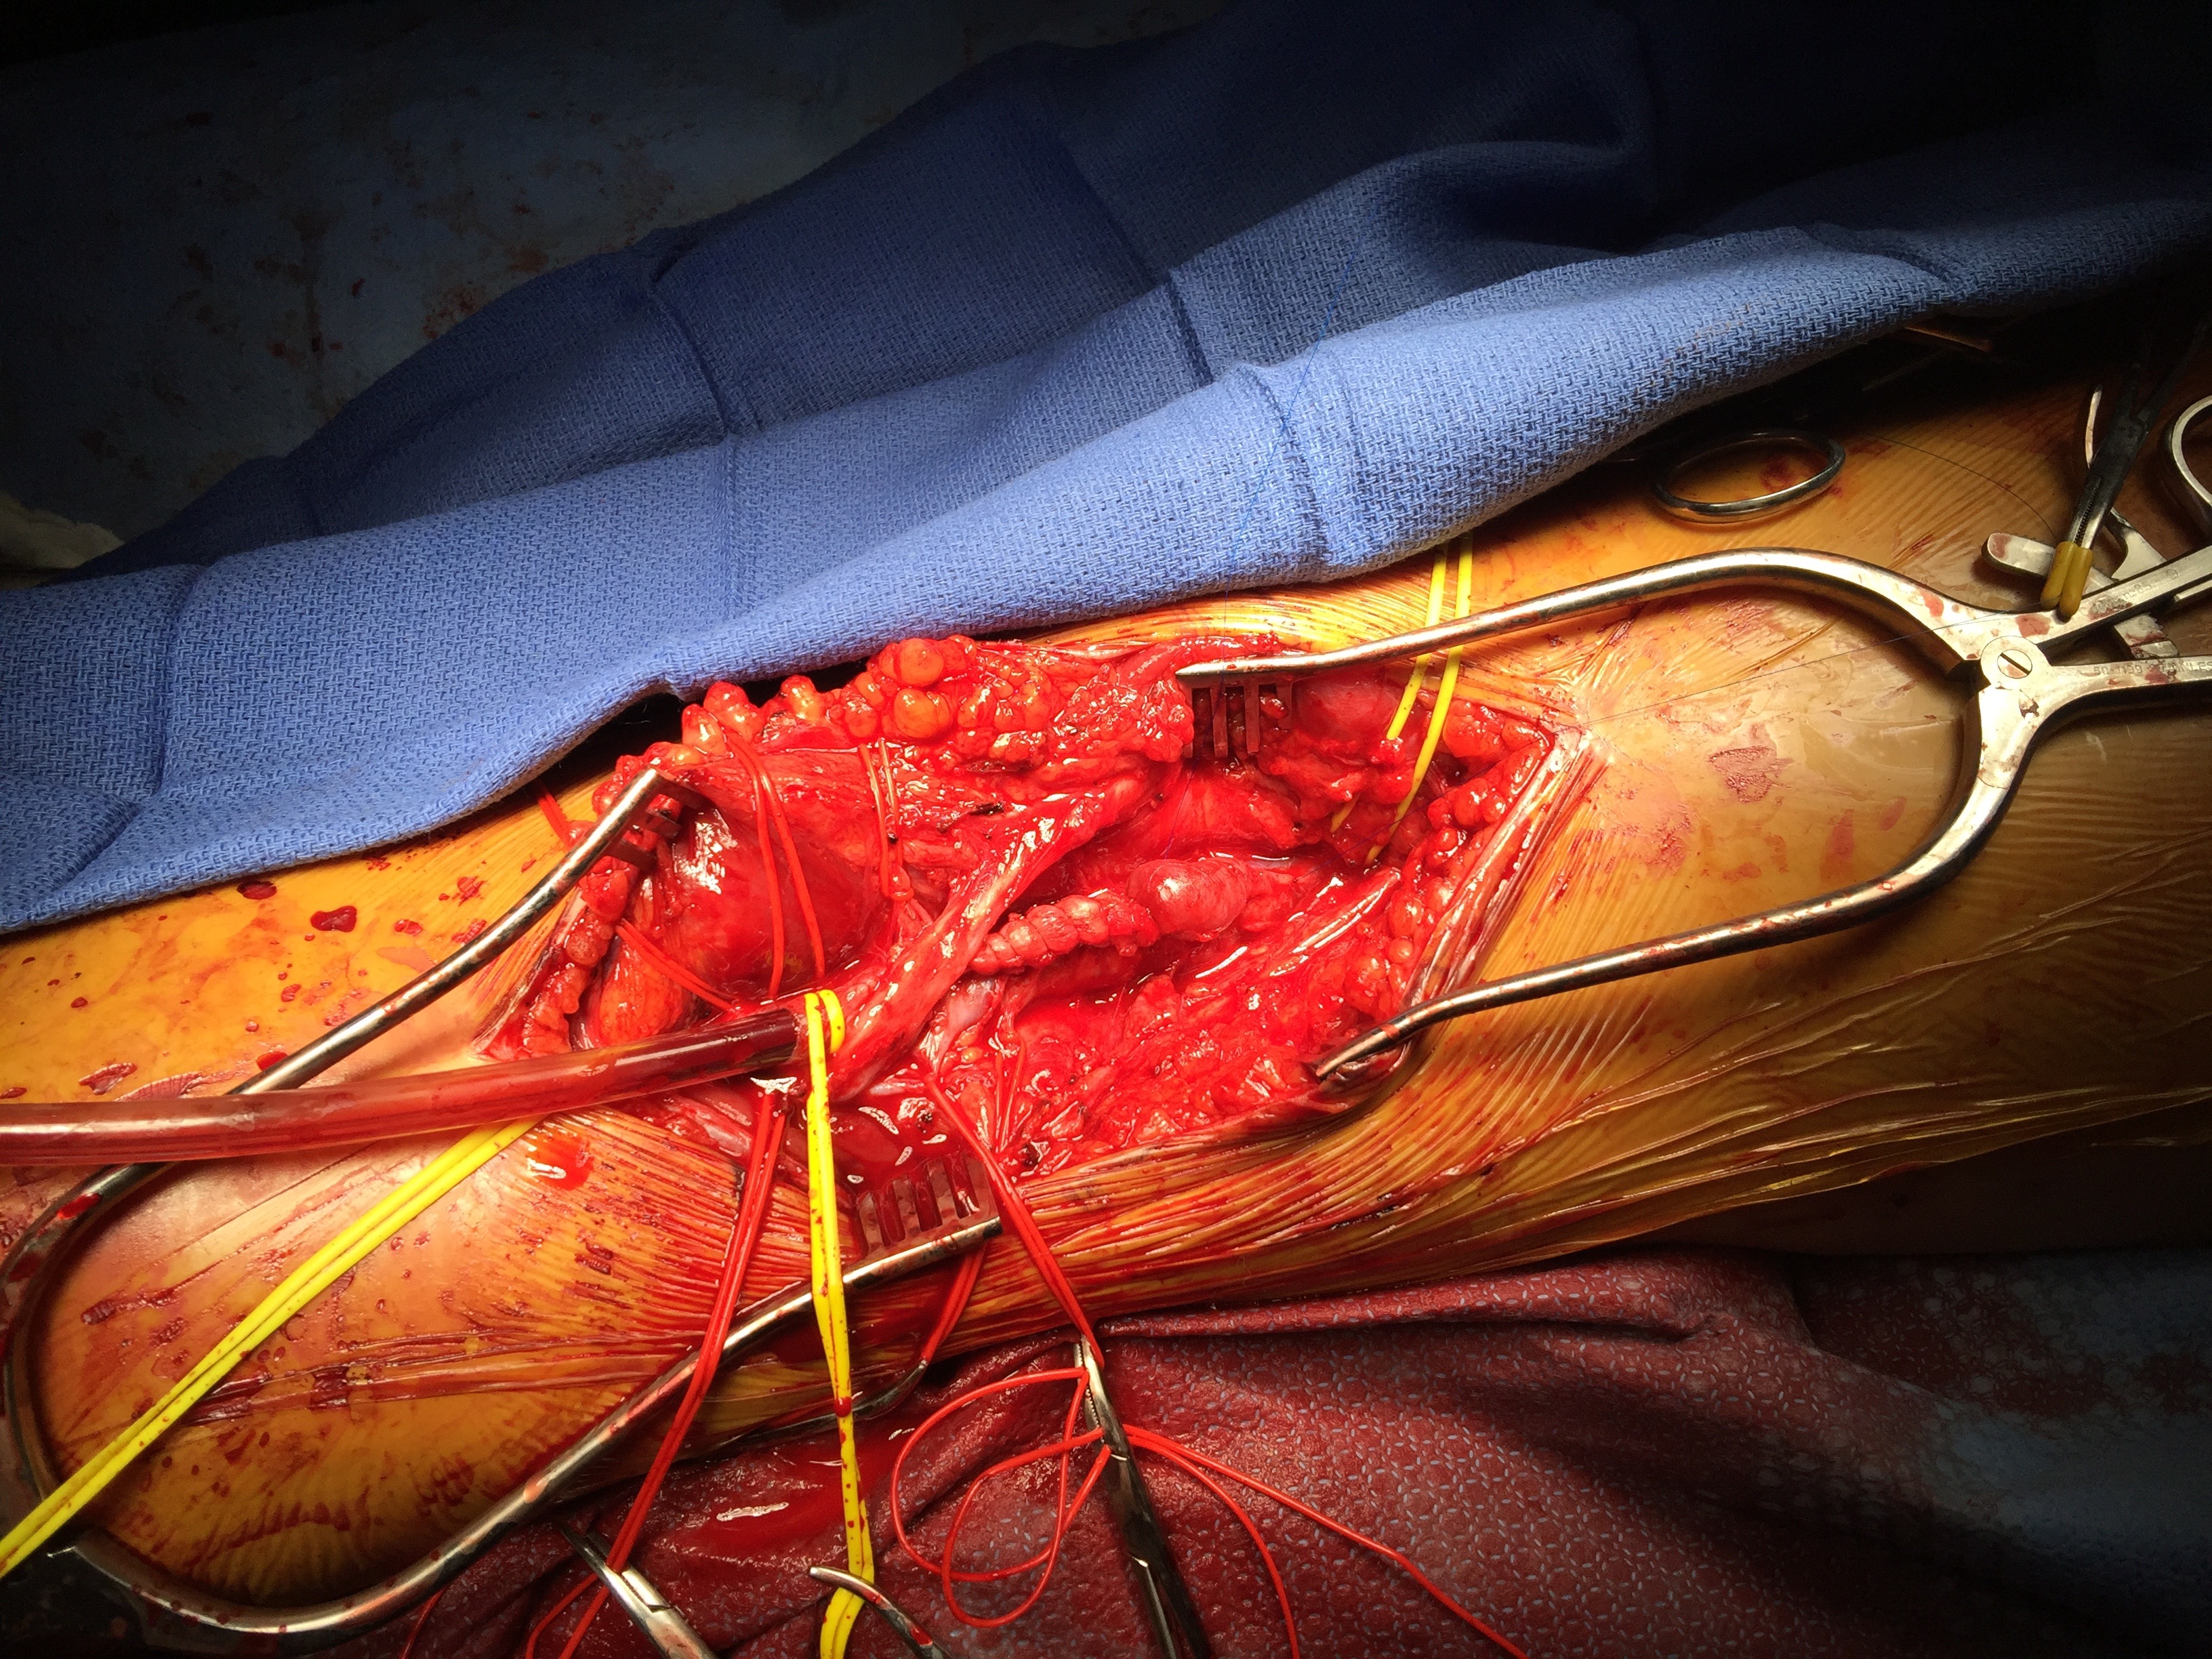

IMG_9702.jpg

A curvilinear incision (lazy S) was made across the popliteal fossa and careful dissection revealed the aneurysm. It was soft and the vein was normal below in the calf. Above it, there was a tight fibrous band that was contricting it -a popliteal venous entrapment. I released this band. Using a 24 French Foley catheter inserted through a transverse venotomy on the popliteal vein below, the aneurysm was plicated to approximately 1cm diameter, and the catheter removed and the venotomy repaired.

IMG_9703

The nerves were restored to their original position and the wound closed in layers. She recovered well and returned to followup about a month later. Duplex showed a patent vein and she had no symptoms of dyspnea.